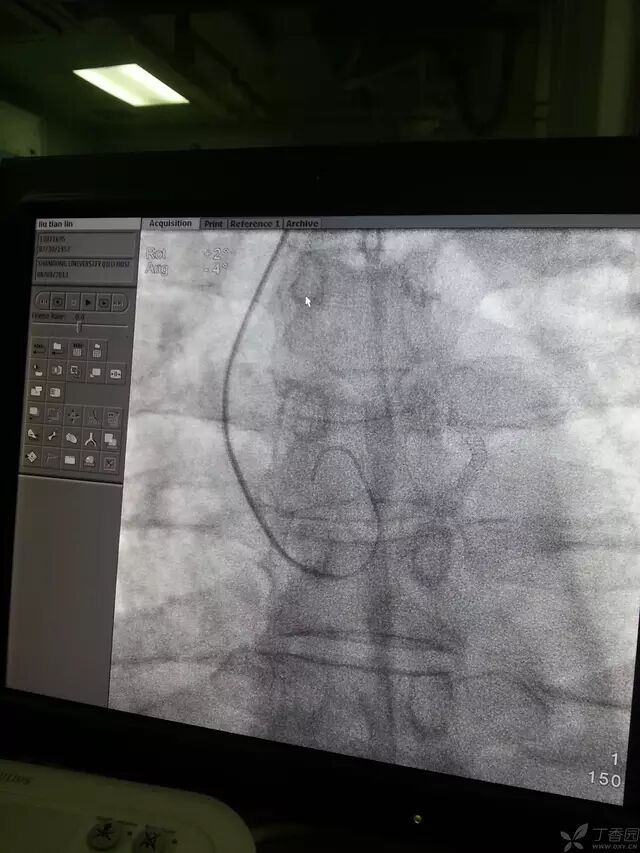

可嘱病人深吸气并憋住,一般导丝可顺利进入升主动脉,下降至窦底,使导丝盘成 L 型时,如下图。

造影导丝是什么原来心脏造影这样做:冠脉造影全程图解_https://www.jmylbn.com_新闻资讯_第12张